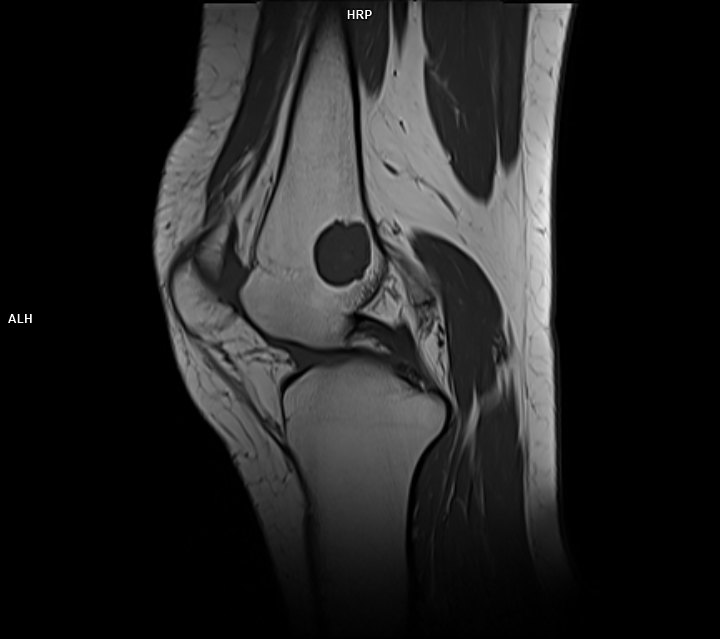

CAZ nr 44 Encondrom femural distal

Figura 4: achiziție în plan sagital în ponderație T1

Discuție caz nr 44: Encondromul este o tumora benignă cu origine cartilaginoasă; cazul prezentat evidențiază o leziune net delimitată în hipersemnal PD, hiposemnal T1, fără restricție de difuzie, ce nu modifica semnalul țesutului osos de vecinătate si se dezvoltă de o parte şi de alta a cartilajului de creștere.